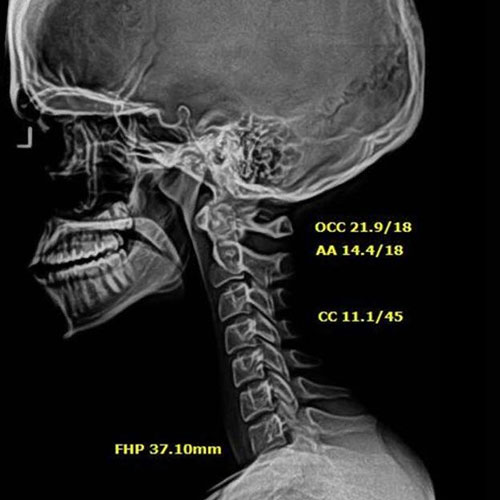

In this case, initial cervical spine X-rays revealed a significant loss of normal neck curvature, a condition that places excessive strain on the spine and nervous system. When the cervical curve is reduced, the head shifts forward, increasing stress on spinal joints, discs, and nerves — often leading to chronic neck pain, headaches, migraines, and neurological symptoms.

Before Chiropractic Treatment: The patient’s X-rays showed a flattened cervical curve, meaning the neck was no longer supporting the head in its ideal position. This type of misalignment is commonly linked to long-term spinal degeneration, nerve irritation, and persistent symptoms that don’t resolve with medication alone.

When spinal structure is compromised, the body is forced to compensate — and over time, those compensations break down.